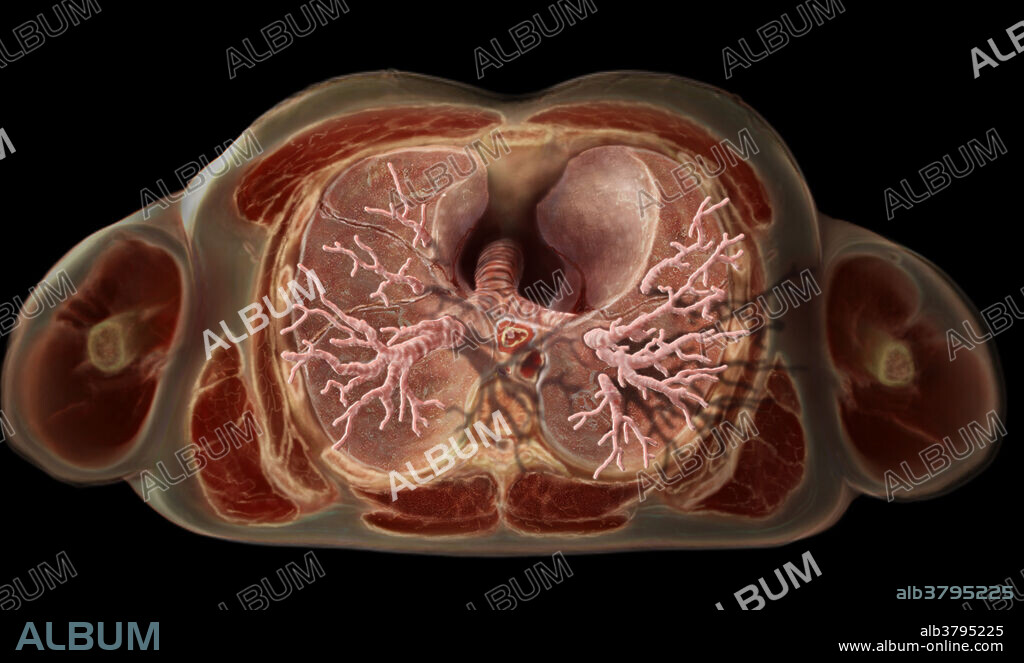

Inferior view of a transverse section of the thorax, highlighting the lungs. The trachea, cardiac impression, and transverse sections of the thoracic aorta and esophagus are visible, as is the bronchial tree. When air is inhaled into the lungs, it flows through large tubes called bronchi, then branches into smaller tubes known as bronchioles, and ends up in the alveoli, small pouches in the respiratory system where oxygen is transferred from the air to the bloodstream.